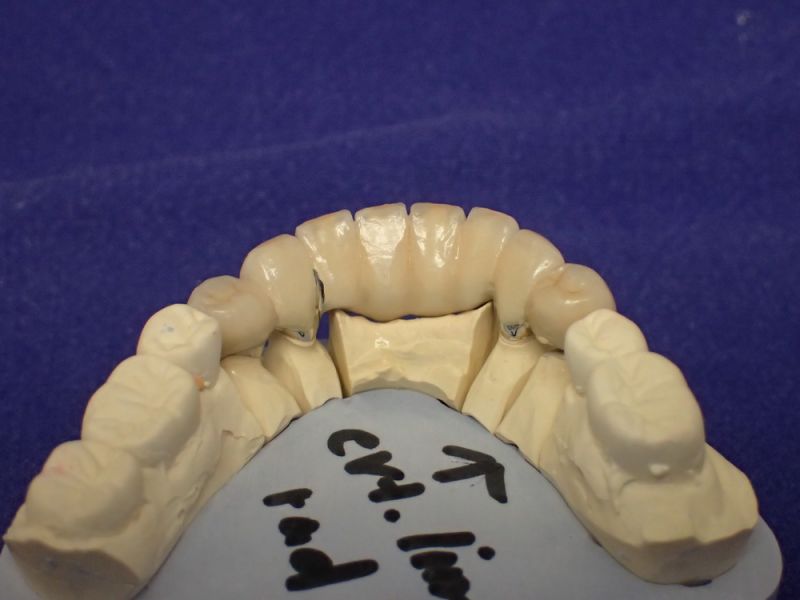

Langjährige Kieler Patientin erhält neue Unterkieferfrontzahnbrücke

Die Oberkieferteleskoparbeit hat die Patientin inzwischen fast 25 Jahre im Mund und die Unterkieferfronzahnbrücke könnte das ebenfalls erreichen.